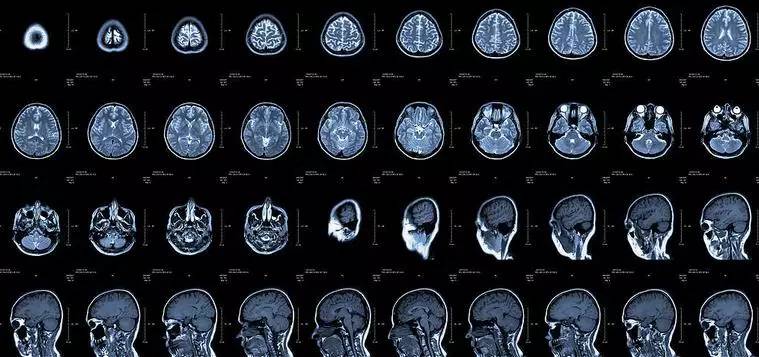

核磁共振:搖一搖再看

核磁共振機使用較強大的磁場,使人體中所有水分子磁場的磁力線方向一致,這時磁共振機的磁場突然消失,身體中水分子的磁力線方向,突然恢復(fù)到原來隨意排列的狀態(tài)。簡單說就相當(dāng)于用手搖一搖,讓水分子振動起來,再平靜下來,感受一下里面的振動。所以,核磁共振(MRI)也被戲說為是搖搖看的檢查。